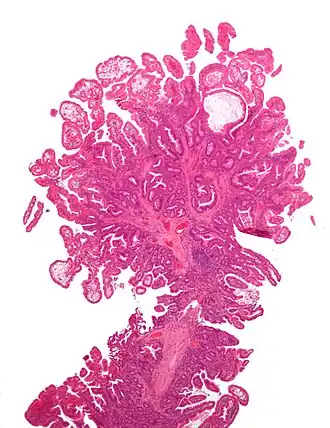

| Micrografia de um pólipo colorretal do tipo Peutz-Jeghers; coloração H&E. | |